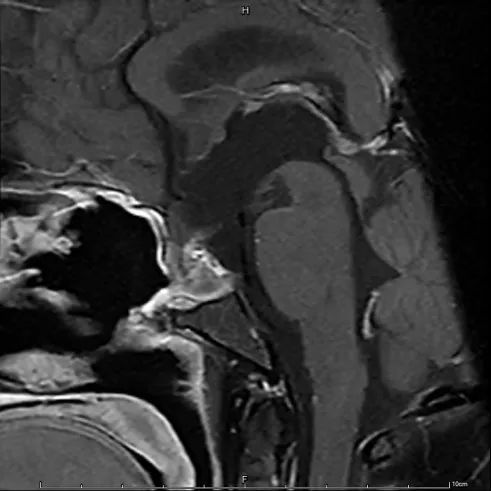

经过完善的术前检查后,垂体泌乳素瘤诊治中心对患者开展手术治疗。手术进行了五个小时,如患者所期待的那样,肿瘤获得了比较圆满的一次性全切,术后下丘脑反应亦平稳可控,鞍底修补严密,在2周的住院护理恢复后,患者如期出院。

黄女士术前(左)术后(右)影像对比

位于鼻腔内的微创伤口,没有干扰到黄女士正常的生活,也没有影响人际交往。毕竟对于年轻女性来说,外表终究是一个值得珍惜的职场要素,手术频次更是需要考量的“经济效益”,此次治疗结果是患者心目中最为理想的。出院后,特意送上锦旗的黄女士,一改不响和低调作风,只为点赞瑞金医疗团队高超的技术。